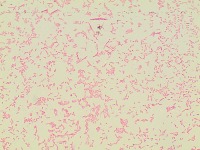

bacterial-image-classification Computer Vision Project

bacteriaclassification

Classes (78)

A description for this project has not been published yet.